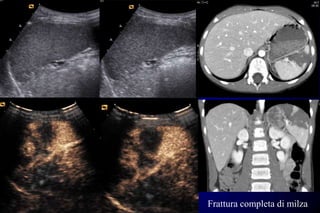

Lesione splenica di III grado “affiorante”

Frattura completa di milza